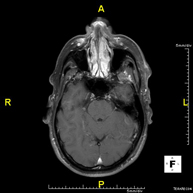

- Neuroradiology

- Brain MRI (cranial)

This non-invasive diagnostic procedure uses an electromagnetic field and radio waves (from a transmitter and receiver) to acquire high-definition anatomical images of the brain. It is a radiation-free procedure. Indicated for: vascular problems, memory loss, epilepsy, headache, malformations, suspected tumour, meningitis.